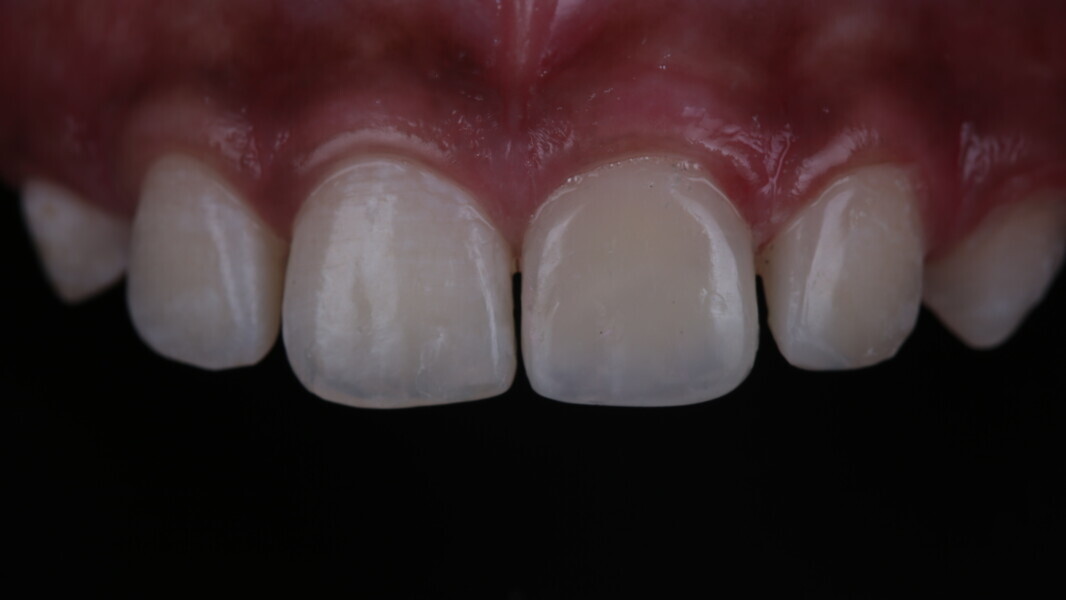

A 10-year-old male patient reported with a complaint of trauma to the upper left central and lateral incisors, involving the enamel and dentin. Direct composite was used in multi-layers and the smile was restored. This article explains detailed steps in the polychromatic layering technique with special emphasis on the finishing and polishing protocol. 3M Espe Filtex Z350 Xt was used with a universal bonding agent.

Fig 31-41: Polishing protocol and post-op